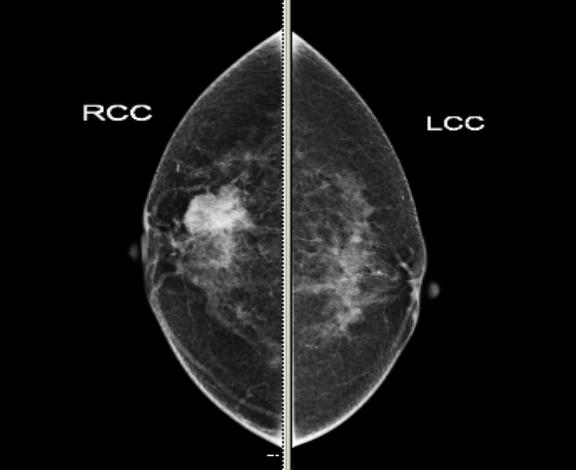

▲高清晰度的平板数字乳腺钼靶影像

与传统乳腺钼靶机相比,全数字化平板乳腺钼靶作为一种无创性的检查手段,采用全新的光学转换技术,1300万像素的图像细节更清晰,此项指标目前是业界最高水准之一,在诊断中能够轻松捕捉到0.1毫米的细微钙化病灶(微小钙化灶对乳腺癌的诊断具有重要意义),使组织层次更丰富,图像能清晰地显示病变的特征及病变与周围组织的关系,组织分辨率较传统钼靶摄影大大提高,在低剂量投照条件下保证了优异的图像质量,使受照剂量能够减少40%-60%照射剂量,对人体损害降到最小,该设备是美国FDA唯一批准能够进行定期筛查的检查设备。同时,强大的图像后处理功能可以将皮肤、皮下脂肪、浅静脉及Cooper韧带、腺体、导管及淋巴结结构等清晰显示在图像上,便于观察整个乳房的所有正常结构及病变组织,是乳腺检查不可或缺的检查手段。

早期乳腺癌特别是导管内癌,往往可在钼靶摄片上看到一小簇不规则钙化点或微小钙化灶,因而数字钼靶摄片堪称早期乳腺癌的“照妖镜”,由于以往钼靶机的图像质量较差不能够发现早期的微小钙化,从而影响诊断的准确率和钙化的检出率,所以只有高质量的平板数字钼靶机才具备较高的空间分辨率和较好的组织分辨率,乳腺癌的早期检出和诊断成为可能,进而使医生在更早的时间实施更有效的治疗,对降低乳腺癌死亡率方面起着关键作用,因此平板数字钼靶摄影成为国际卫生组织公认的唯一有效的、最简便、最可靠的无创性乳腺疾病筛查手段。